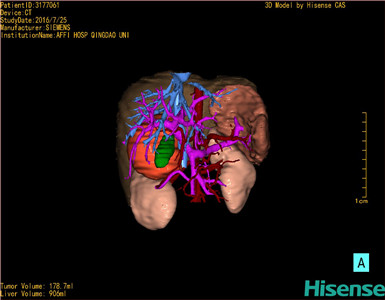

将0.625mm双源薄层CT资料的静脉期和动脉期Dicom格式文件导入海信CAS系统。

通过调节窗宽窗位调整CT序号,对肿瘤,肝实质,胆囊,下腔静脉,肿瘤,肝动脉、门静脉及肝静脉等进行三维重建;系统自动计算肿瘤体积和肝脏体积。

模拟手术操作,自动计算切除肿瘤体积。肝脏体积为906ml,肿瘤体积为178.7ml,肿瘤体积为肝脏体积的19.7%,通过比对6-9月正常肝脏体积为257.75±51.05ml,通过术前模拟手术,精准判断切除后剩余肝脏体积能耐受,避免肝衰竭发生。

术前三维重建:

重建图片